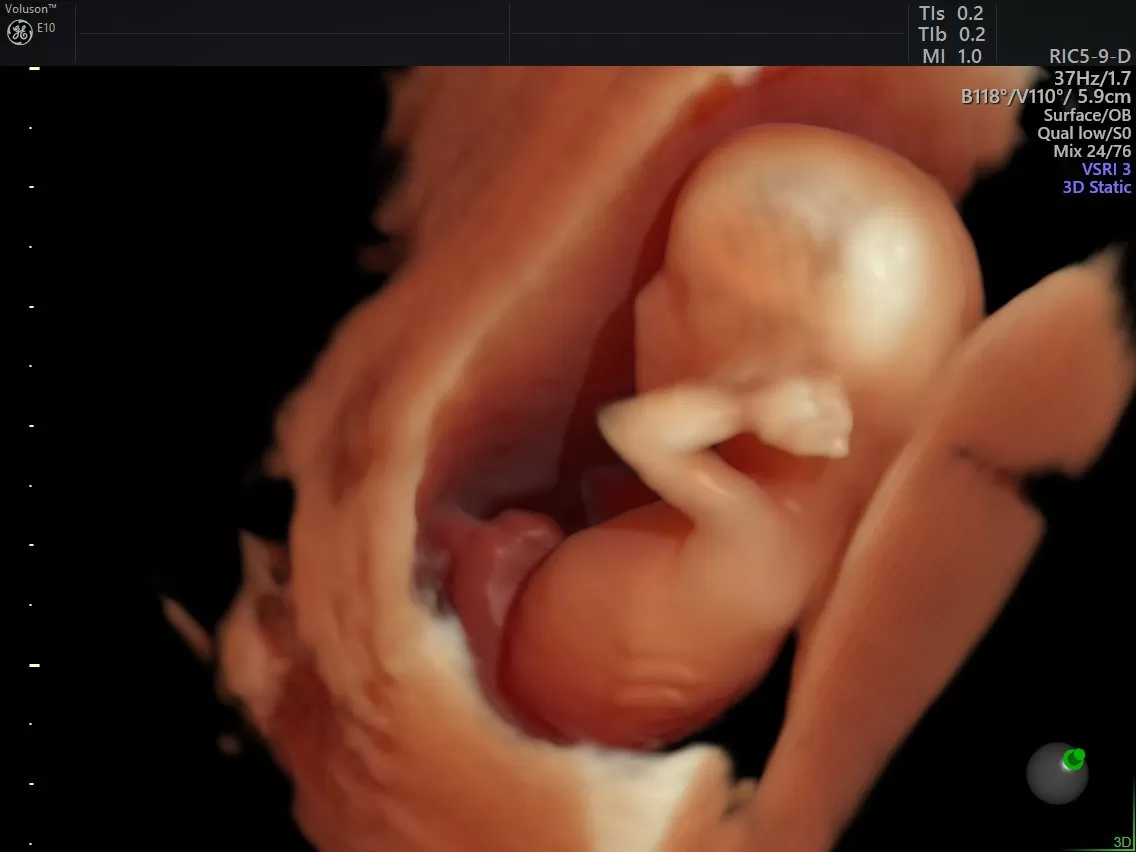

Семья Маловых приняла участие в телепроекте "Я стесняюсь своего тела". Более десяти лет пара не могла забеременеть, а также врачи не смогли поставить точный диагноз Надежде Маловой. Сейчас Надежде предстоит обследование, чтобы определить тактику лечения.